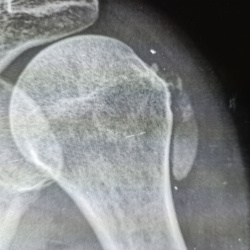

Женщина 1991 г р. Проходила флг, доктор увидел в плечевой кости доп.тень отправил на рг. доктора подскажите пожалуйста что это может быть?

Девушка 31 год. Сделали блокаду (со слов) неделю назад в Ч/К. Болеть не перестало. Выписок никаких нет. Коллеги подскажите пожалуйста, что это параартикулярно в мягких тканях?